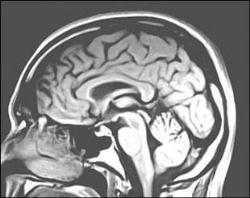

عصب شناسها تلاش می کنند پروژه بزرگی را اجرا کنند که طی آن نقشه فعالیتهای مغز روشن شده و این نقشه به طور بالقوه می تواند علل افسردگی، اسکیزوفرنی و دیگر اختلالات سلامت روانی را مشخص کند.به گزارش خبرگزاری مهر، پروژه نقشه فعالیت مغز در مراحل طراحی است.

عصب شناسها تلاش می کنند پروژه بزرگی را اجرا کنند که طی آن نقشه فعالیتهای مغز روشن شده و این نقشه به طور بالقوه می تواند علل افسردگی، اسکیزوفرنی و دیگر اختلالات سلامت روانی را مشخص کند.به گزارش خبرگزاری مهر، پروژه نقشه فعالیت مغز در مراحل طراحی است. شش دانشمند در شماره ژوئن 2012 مجله نورون پیشنهادهای وسیع را برای توسعه حسگرهای غیر تهاجمی و شیوه های مختلف برای آزمایش روی سلولهای واحد در شبکه های نورونی مطرح کرده اند.

این پروژه نظری در شماره آخر مجله ساینس اهداف نهایی خود را تشریح کرده است. این محققان اظهار داشتند که طی چندین سال متمادی باید کارهای زیادی برای ارائه روشهای رصد یک میلیون نورون انجم شود. هدف نهایی این پروژه درک چگونگی کارکرد شبکه های مغز است.

درحال حاضر محققان می توانند فعالیتهای یک نورون واحد را با استفاده از الکترودها مشاهده کنند. آنها می توانند کل مغز را با استفاده از تصویرسازی تشدید مغناطیسی کارکردی (fMRI) و سایر تکنیکها مشاهده کنند اما نحوه کارکرد الکترونها درکنار هم در شبکه ها و این که وقتی مدار مغز متلاشی می شود چه اتفاقی رخ می دهد مشخص نیست.